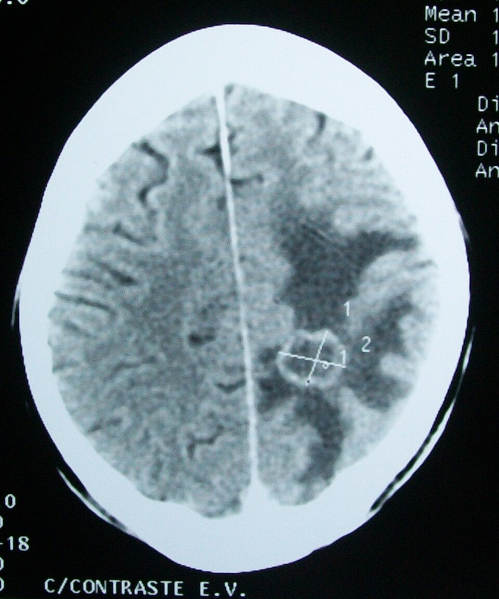

In 1970, a fungal substance, called verticillin A, had been discovered and been considered as an anti-cancer agent. However, only now it has been achieved to synthesize it and also to build molecular variants of it which show promise against aggressive forms of brain cancer in children.